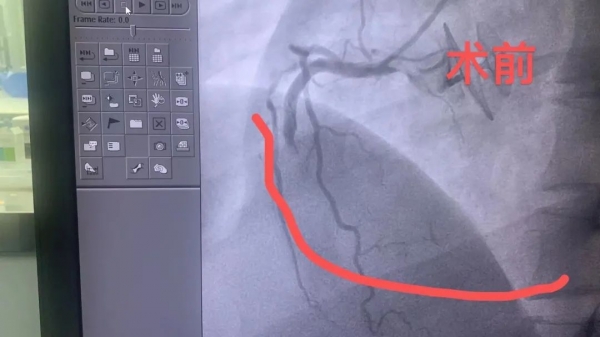

急診行心電圖示:下壁ST段抬高,診斷為急性下壁ST段抬高型心肌梗死。立即啟動胸痛中心綠色通道,給予救治。田豐主任帶領(lǐng)的團隊緊急在局麻下行冠狀動脈造影術(shù)+經(jīng)皮冠狀動脈球囊擴張成形術(shù),手術(shù)順利完成。